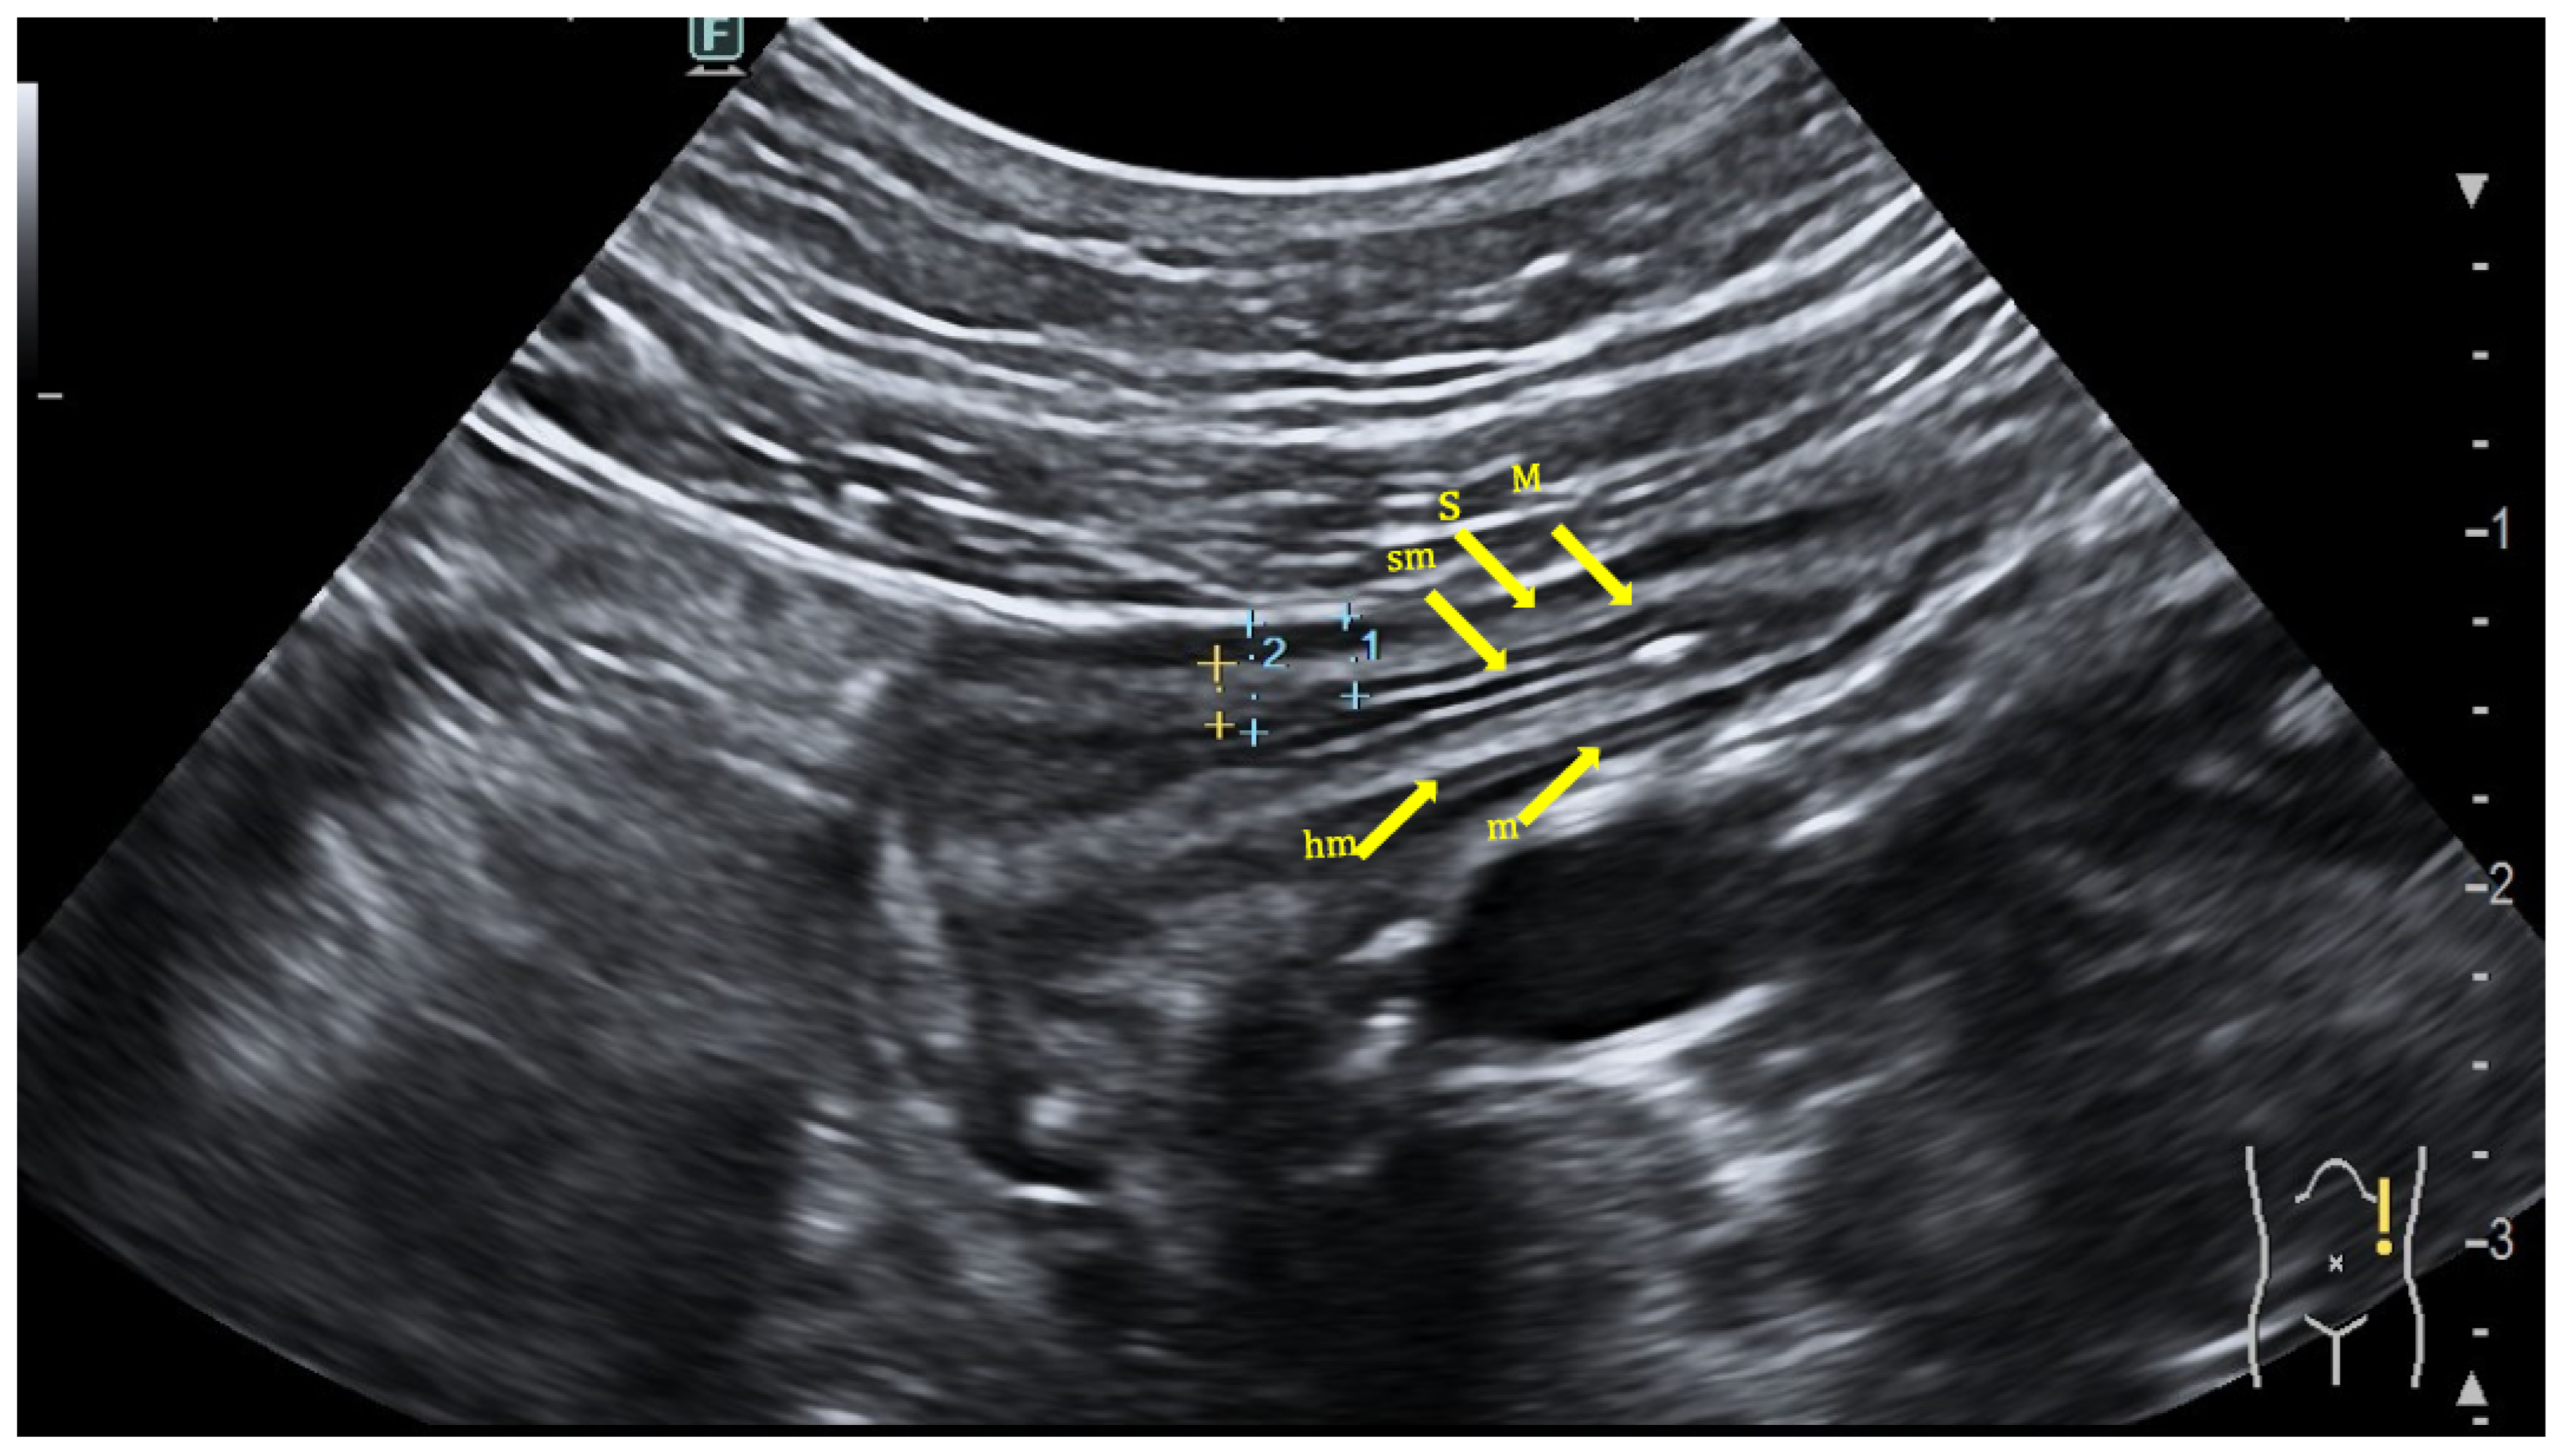

2.1. Colonic Evaluation